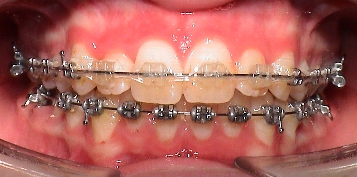

ขณะเข้ารับการรักษา ผู้ป่วยอายุ 11 ปี มีขากรรไกรล่างที่หลุบถอยไปด้านหลังอย่างมาก และถูกฟันหน้าบนกลางที่งุ้มเข้าครอบปิดทั้งหมด จะมองไม่เห็นฟันตัดล่างเพราะมีภาวะสบลึก กระดูกขากรรไกรบนและล่างเล็กอันจะสังเกตได้จากฟันหน้าบนและล่างซ้อนเกอย่างเห็นได้ชัด

ผู้ป่วยมีภาวะฟันสบเหลื่อมชนิด Class II Division II Overbite ได้รับการรักษาแบบหลายขั้นตอน ในขั้นแรกใช้เครื่องมือกระตุ้นแอกติเวเตอร์ KI II 2 และต่อมาใช้เครื่องกระตุ้นเพื่อจัดฟันแบบของ Prof. Sander (VDP) และเครื่องมือจัดฟันชนิดติดแน่น โดยใช้เครื่องมือจัดฟันชนิดถอดได้นาน 23 เดือน และเครื่องมือชนิดติดแน่น 17 เดือน

เครื่องมือจัดฟันชนิด มัลติแบนค์ ที่ใช้ในผู้ป่วยรายนี้